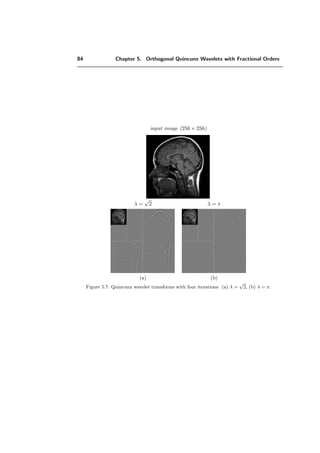

5.5 Experiments . . . . . . . . . . . . . . . . . . . . . . . . . . . . . . . . . . . 83

5.5.1 Benchmark and testing . . . . . . . . . . . . . . . . . . . . . . . . . 83

5.5.2 Dependence of the order parameter . . . . . . . . . . . . . . . . . . 86

5.5.3 Approximation properties . . . . . . . . . . . . . . . . . . . . . . . . 86